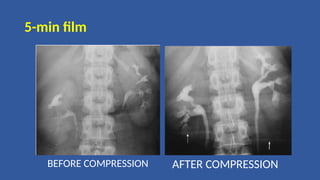

5- minute film

• 5 minute film shows nephrogram, renal pelvis, upper part of ureter

• Compression band is now applied on patient's abdomen and the

balloon is positioned on anterior superior iliac spine where ureters

cross pelvic brim. This is to produce better pelvicalyceal distension

• Compression inhibits ureteric drainage and promotes distension of

pelvicalyceal system, optimizing their visualization

5-min film

BEFORE COMPRESSION AFTER COMPRESSION

• #42 a..collecting system is bilaterally underfilled and poorly demonstrated ……. After comprssion was applied ,distension of the collecting system is significantly improved